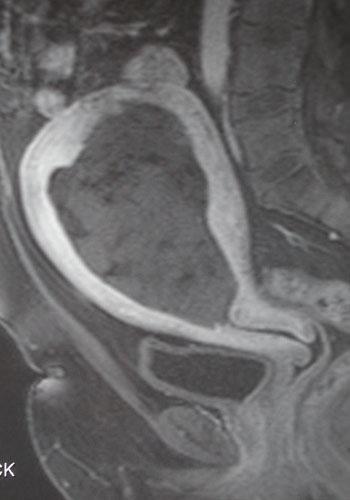

子宫肌瘤栓塞后感染 子宫内膜感染:子宫肌瘤栓塞术后子宫内膜感染的发生率通常在2%~5%。其潜在的机制是由于子宫肌瘤排出,宫颈屏障被破坏,细菌上行,或细菌经血液播散。尽管轻微的子宫内膜感染可以通过口服或静脉抗生素加以控制,如果不加处理将有可能进展为子宫积脓、子宫破裂或败血症。子宫切除术可能是感染失控时不可避免的结果,因此早期干预十分重要。如果病人不能对治疗快速反应,需要尽早进行MRI检查。在所有存在发生子宫肌层损伤及子宫积脓可能的病例中,MRI可能可以明确诊断。如果MRI显示有提示感染的弥漫性子宫异常的证据,且病人有败血症并对早期复苏无反应,则有行急诊子宫切除的指征。 与之类似,在栓塞后子宫肌瘤通过宫颈期间可能会出现经期外出血,甚至严重出血。尽管有进行再栓塞的可能性,在这种情况下其有效性尚属未知。如果出血不能得到控制,可能需要行子宫切除术。 下图为42岁糖尿病患者,子宫肌瘤栓塞后5个月,白带增多和恶臭。MRI显示腔内子宫肌瘤感染(infected intracavitary fibroid),难以吸收,需要清宫。